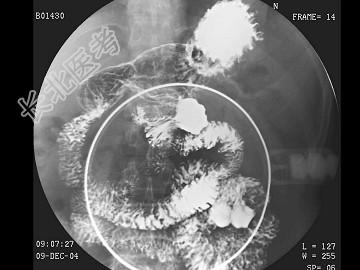

- 单项选择题男,46岁, 腹部不适多年,结合图像, 最可能的诊断为 ( )

A、正常空肠

B、空肠结核

C、克罗恩病

D、空肠多发憩室

E、空肠占位